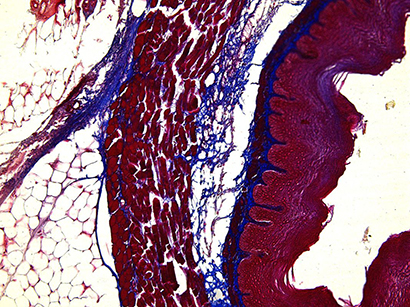

Azan staining is often used to mark connective tissue e.g. of the ear. Brightfield (5x)

Azan staining of the ear with higher magnification (20x). Brightfield

Azan staining of the ear with higher magnification (40x). Brightfield